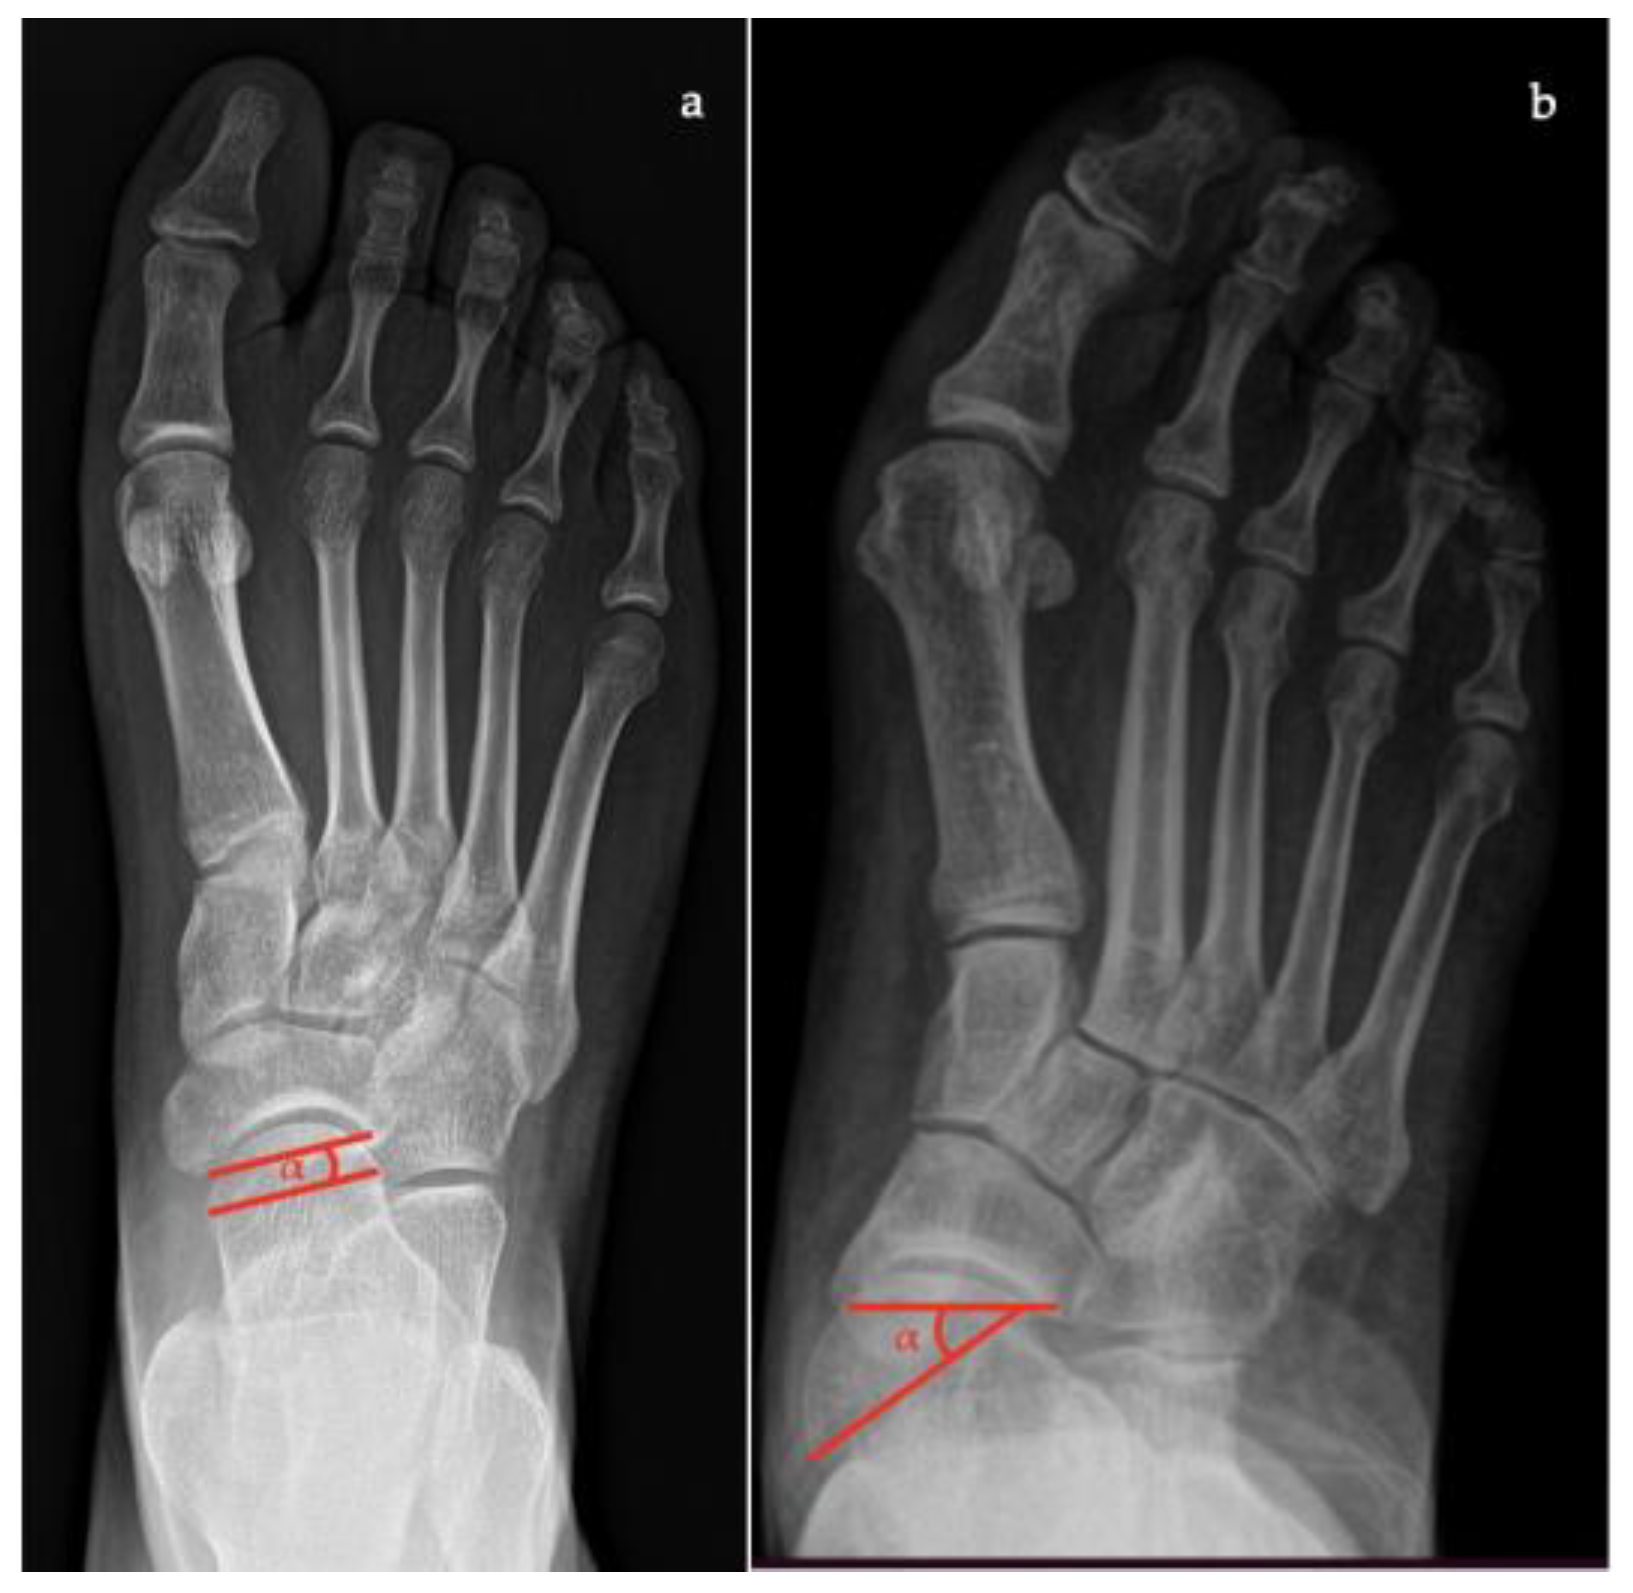

- Talonavicular coverage angle, between the line that joins the medial and lateral articular margins of the talus, and the line that joins the medial and lateral articular margins of the navicular, it represents forefoot abduction (normal, <7°; flatfoot, >7°) (Figure 2);

- Talonavicular uncoverage percentage, the percentage of the talus that is not in contact with the navicular medially, useful to evaluate forefoot abduction (normal, 10% to 30%; flatfoot >30%) (Figure 3);

- Talar incongruency angle (normal, 5° = –26°; flatfoot >26°), is formed by the intersection between a line from the most lateral point of the articular surfaces of the talus and the navicular, and a line from the lateral aspect of the talar neck (in its most narrow segment) to the lateral point of the talar articular surface (Figure 4).